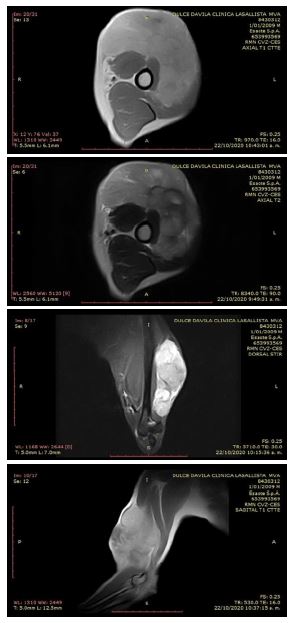

Como resultado de la resonancia magnética se encontró una masa heterogénea en la cara craneal del brazo, con extensión medial y lateral de 10.2 x 8.8 x 5.5 cm, superficial a los músculos braquial y bíceps, con desplazamiento caudal del tríceps, y sin aparente infiltración muscular. La masa tenía contornos lobulados, hiperintensa al músculo estriado en T2 y STIR, ligeramente hiperintensa al musculo en T1 y con realce homogéneo con el medio de contraste, así como un área de necrosis. No se observaron signos de sangrado ni calcificaciones. La lesión presentaba contornos bien definidos y no se observaba compromiso de la topografía del nervio radial, mediano, musculocutáneo y cubital.

Los vasos braquiales no mostraban alteraciones, los músculos con intensidad de señal normal, sin evidencia de lesiones. Los tendones del bíceps y tríceps de apariencia normal. El húmero y lo incluido del cúbito, radio y la articulación del codo no demostraban alteraciones. No había derrame articular en el codo ni se observaban adenopatías (Figura 1).

Figura 1.  Resonancia magnética de una perra Husky siberiana de 11 años. A. Corte axial en T1. B. Corte axial T2, se observa la masas y su proyección. C. Corte dorsal en STIR luego de la administración del gadolinio de forma intravenosa donde se resalta la masas y su extensión. C. Corte sagital en T1